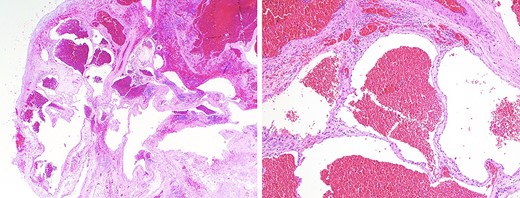

Despite imaging, it may be difficult to differentiate mediastinal hemangiomas from other lesions of the mediastinum without the aid of histopathological confirmation. Histologic features divide hemangiomas into three types: capillary hemangiomas, CHMs, which encompass 90% of cases, and a mixed type [12]. Fig. 2a and2b demonstrates low and medium power views of the lesion, highlighting the presence of endothelial cells lining blood-filled spaces, intervening fibrous stroma, and scattered lymphoid aggregates, diagnostic for CHM. Immunohistochemistry staining was positive for ERD, CD-31, CD-34, confirming a hemangioma and negative for D2-40, effectively ruling out lymphangioma (Fig. 3a and3b).

(a) immunohistochemical staining with antibodies for ERG, an endothelial marker, shows strong and diffuse nuclear positivity in the lining cells of the ectatic blood-filled spaces, confirming the diagnosis of a hemangioma (100X magnification); (b) immunohistochemical staining with antibodies for D2-40, a lymphatic marker, is negative in the lining cells of the ectatic blood-filled spaces, effectively ruling out the differential consideration of a lymphangioma (100X magnification).